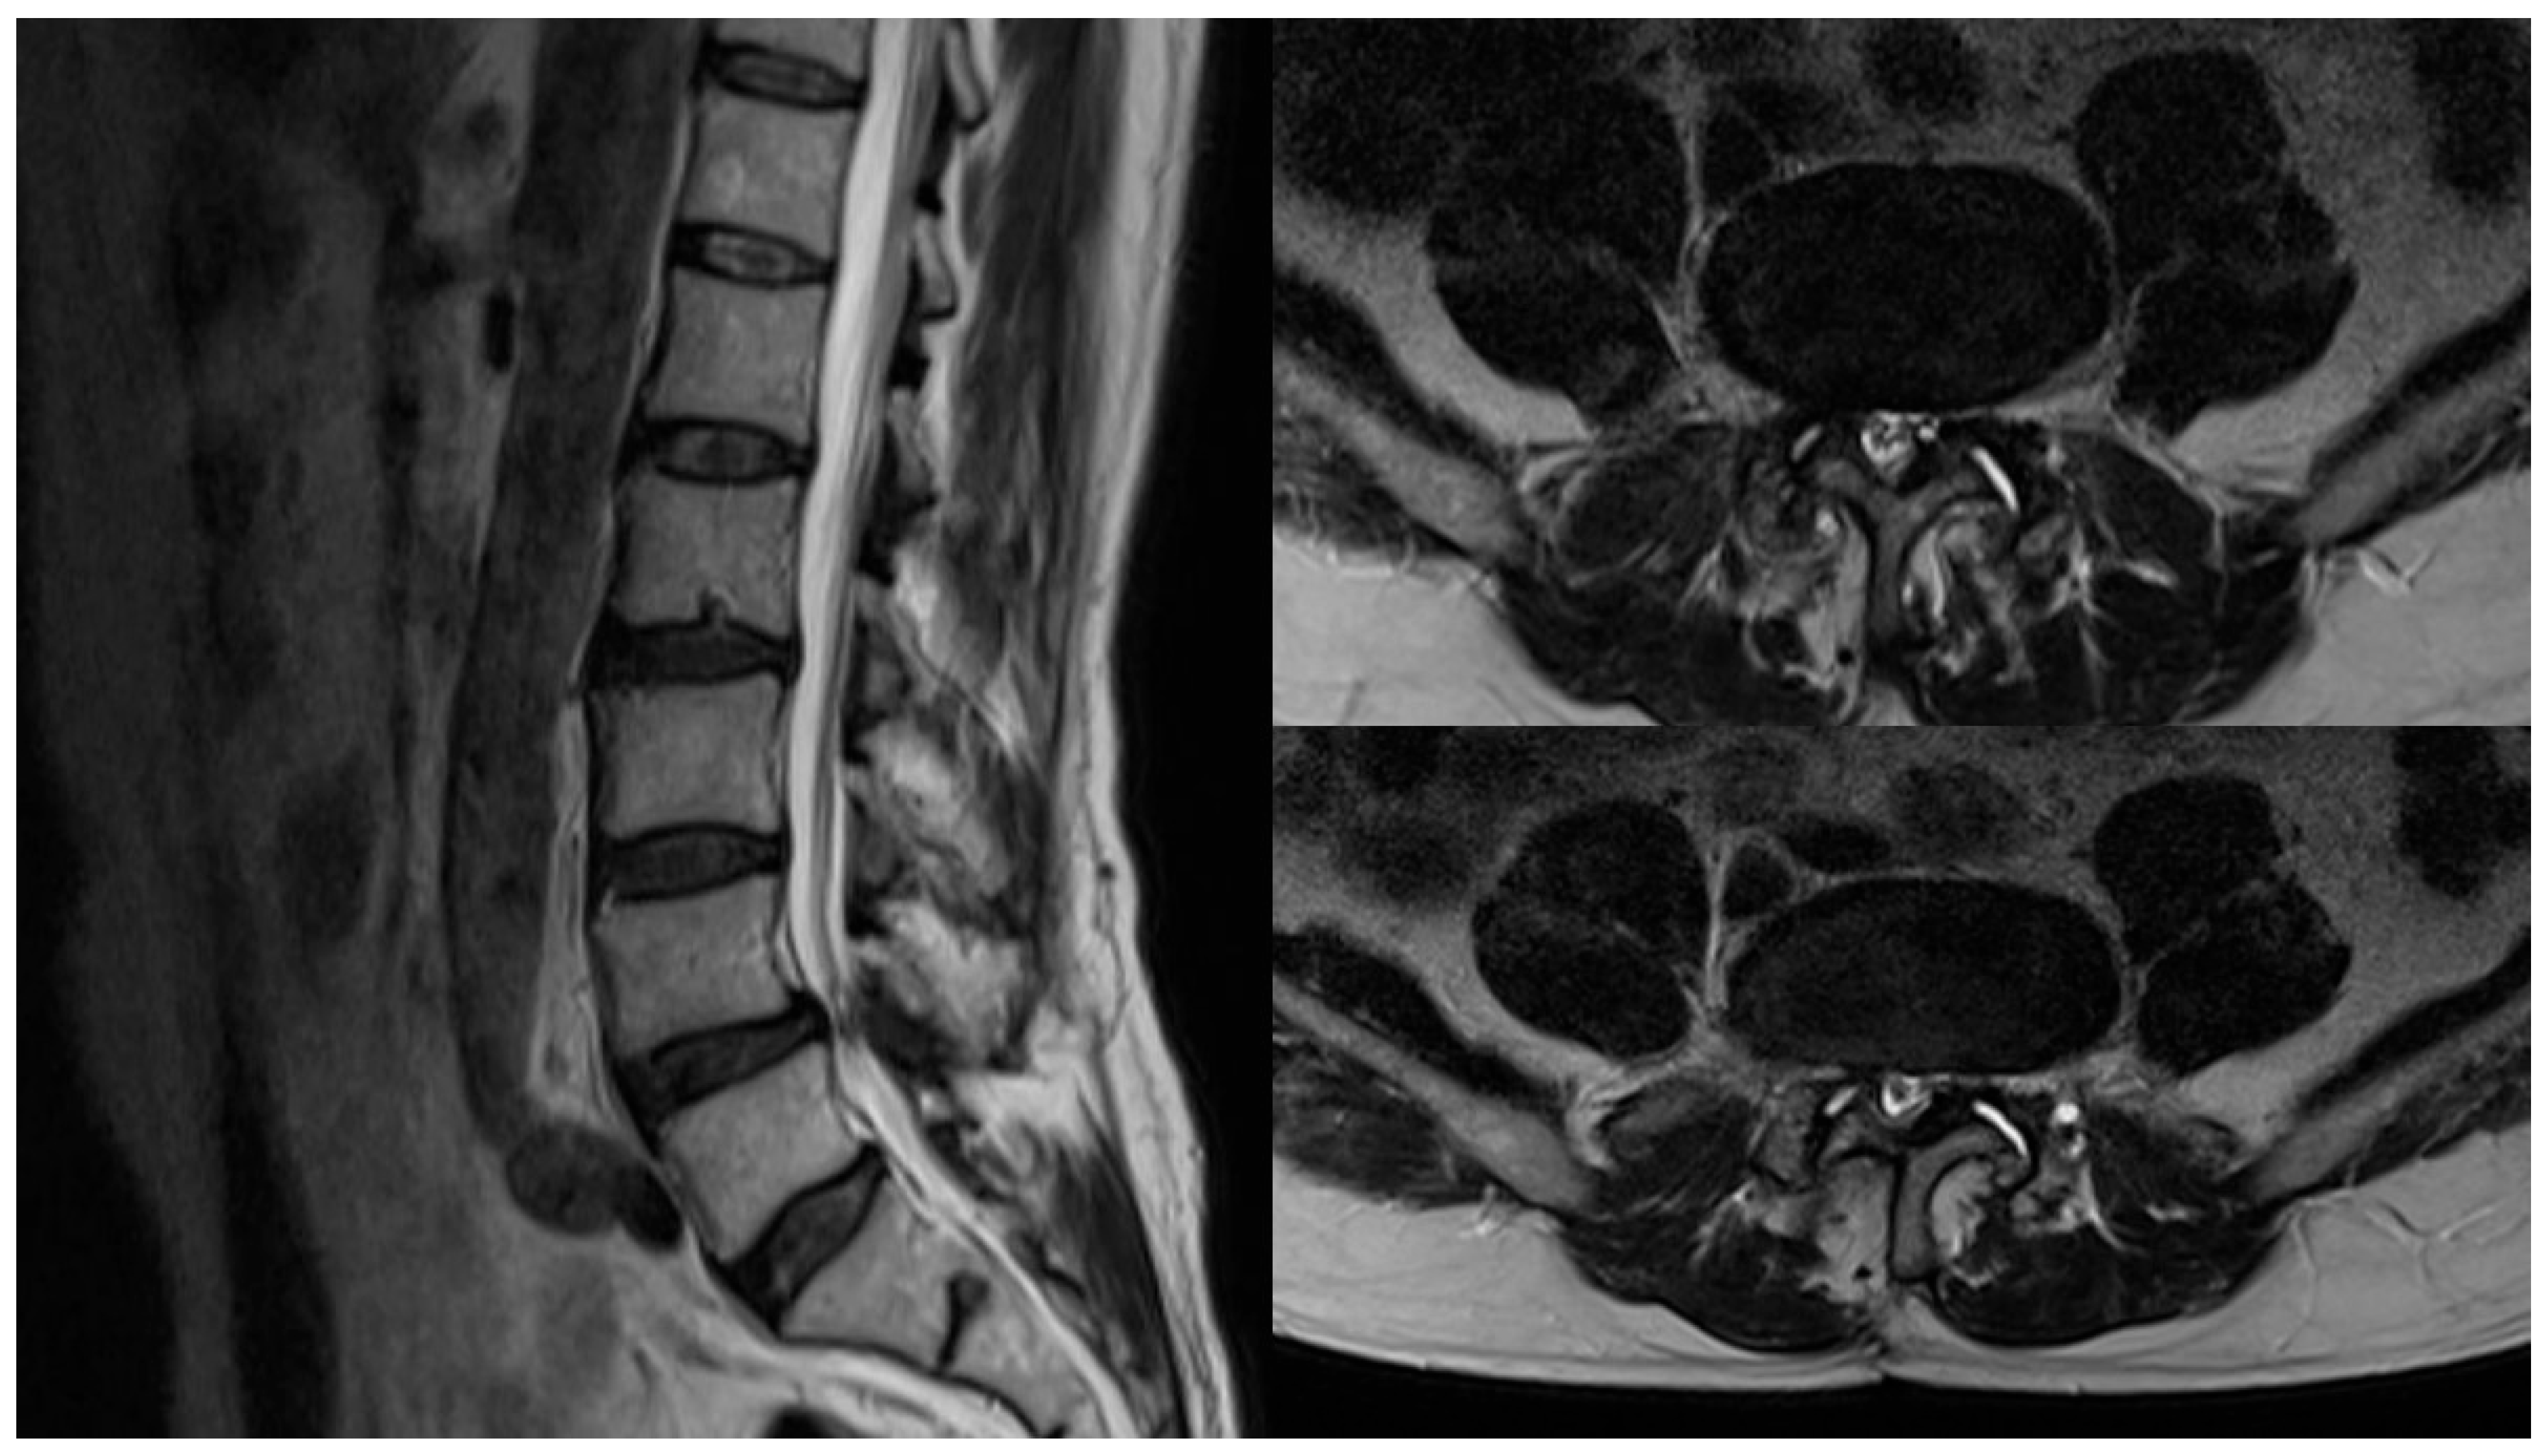

A Rare Case of Posteriorly Migrated Sequestered Lumbar Disc Herniation Through the Interlaminar Space

2. Case Presentation